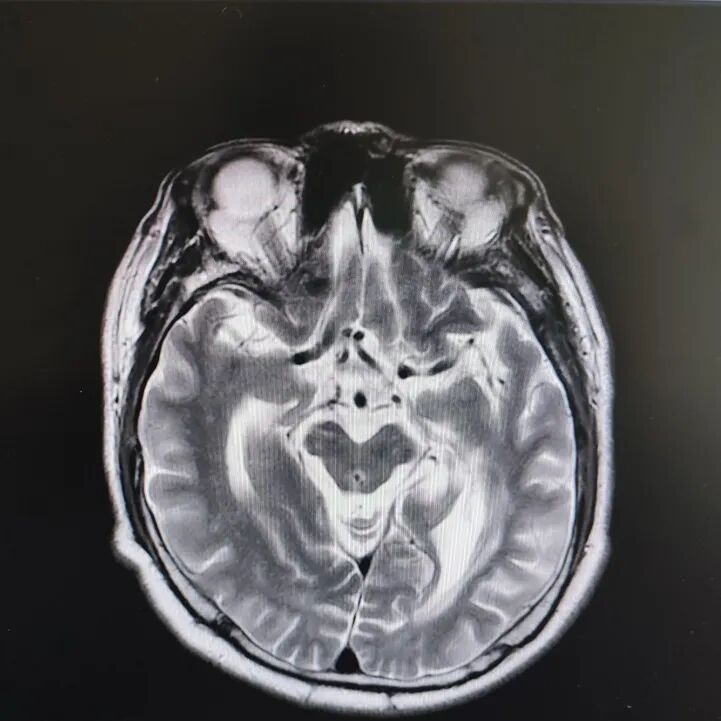

病房里还有另一位患者,来的时候情况更让人揪心:反应迟钝,表情呆滞,行动缓慢。头颅核磁显示脑萎缩明显,但查体发现肌张力、计算力、记忆力、定向力均正常,不符合典型血管性痴呆或阿尔茨海默病表现。

患者头部磁共振影像

凭着多年诊治疑难杂症的丰富经验,赵主任敏锐地意识到这“痴呆”可能是假象,背后另有隐情。他果断建议进一步做特殊感染筛查。果然,检查证实这位患者同样是感染了苍白密螺旋体!经过精准的抗感染治疗,奇迹发生了:患者的反应变快了,眼神灵活了,走路也恢复了正常步态。最终的诊断是“麻痹性痴呆”——一种由神经梅毒引起的、可治疗逆转的“痴呆”类型!